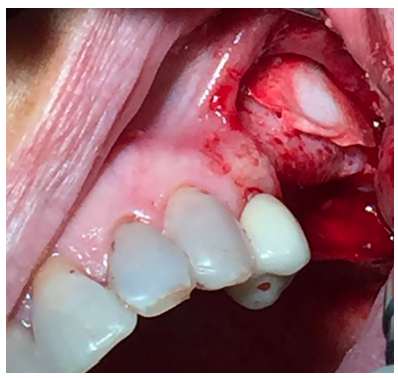

El abordaje quirúrgico fue realizado mediante una incisión lineal crestal y dos descargas verticales, mesial y distal, procediendo al despegamiento mucoperióstico para la obtención de un campo quirúrgico adecuado. Se realizó el diseño de una ventana lateral con piezoeléctrico (VarioSurgery®) (Figura 4), despegándose a continuación la membrana sinusal sin perforación alguna (Figura 5). A continuación, se procedió al relleno mediante un compuesto de fosfato de calcio-potasio-sodio bioactivo (Osseolive®) (Figura 6), acompañado de la colocación de una membrana de ácido poliláctico (EPI-Guide®) (Figuras 7 y 8), finalizando la intervención con la reposición del colgajo mucoperióstico y sutura con poliamida de 4/0 (Supramid®) (Figura 9).